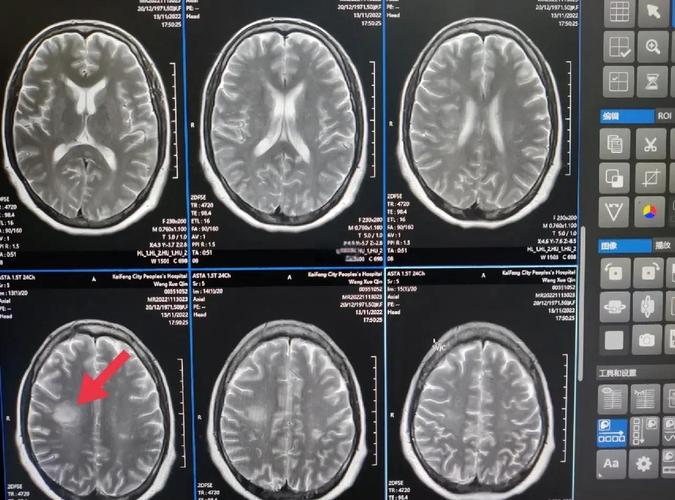

- T1加权像 (T1WI) 和 T2加权像 (T2WI):这是最基本的两个序列。

- 肿瘤:通常在T2像上呈高信号(白色),在T1像上呈低信号(黑色)。

- 脑膜瘤:常紧贴大脑镰或小脑幕生长,在T1像上与脑组织等信号。

- 囊肿:在T1和T2像上都呈非常均匀的高信号,像一个“水泡”。

- 急性出血:在T1像上可能呈高信号。